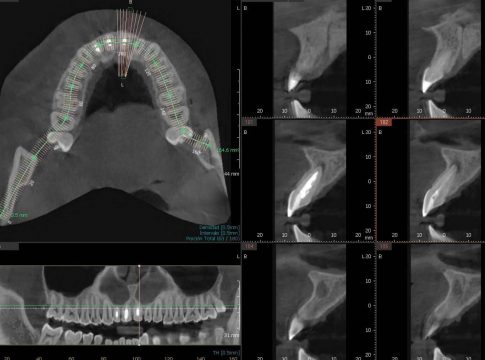

El CBCT dental se diferencia de otros tipos de radiografías dentales porque ofrece una representación más clara, fiel y tridimensional de la estructura dental y resto de maxilares de una persona. Es precisamente su tridimensionalidad la que permite al especialista poder tener una mejor visualización del área, por ejemplo, a nivel inferior, superior, anterior, frontal, etc.

Además, ofrece diferentes niveles de ampliación, con lo cual se logra una visualización muy precisa, entregando una imagen de gran calidad.